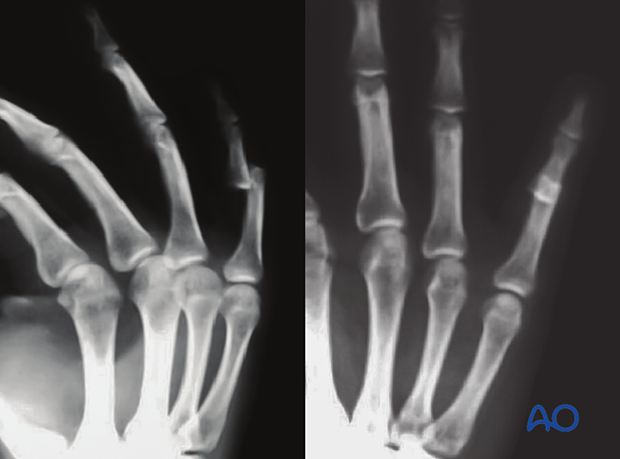

This x-ray shows a palmar dislocation of the PIP joint of the 5th finger.

This x-ray shows relocation of the PIP joint without an associated fracture of the same case.